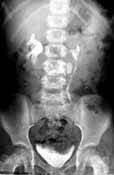

IVU (intravenous urography)

In this, a dye is injected intravenously and x-ray

pictures of the kidneys, ureters and bladder are obtained.

The dye is radio-opaque and seen well with x-rays.

Overnight fasting and good preparation of the colon

with Dulcolax are required.